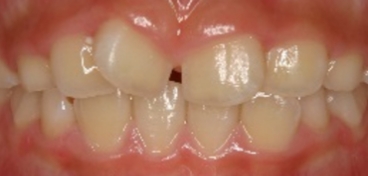

非抜歯矯正(永久歯を抜かずに矯正した場合の変化)

当院では小児期に治療を開始した場合を中心に、できるだけ永久歯を抜歯しないで治療しています。但しそのような場合の術後の様子は、抜歯をした場合とは少し異なるようです。つまり抜歯症例より安定していない感じが、臨床の印象としてはあります。

永久歯を抜かずに矯正できたが、自然な歯並びの変化(犬歯部で狭くなる)のために、下顎前歯にガタツキが発生した。